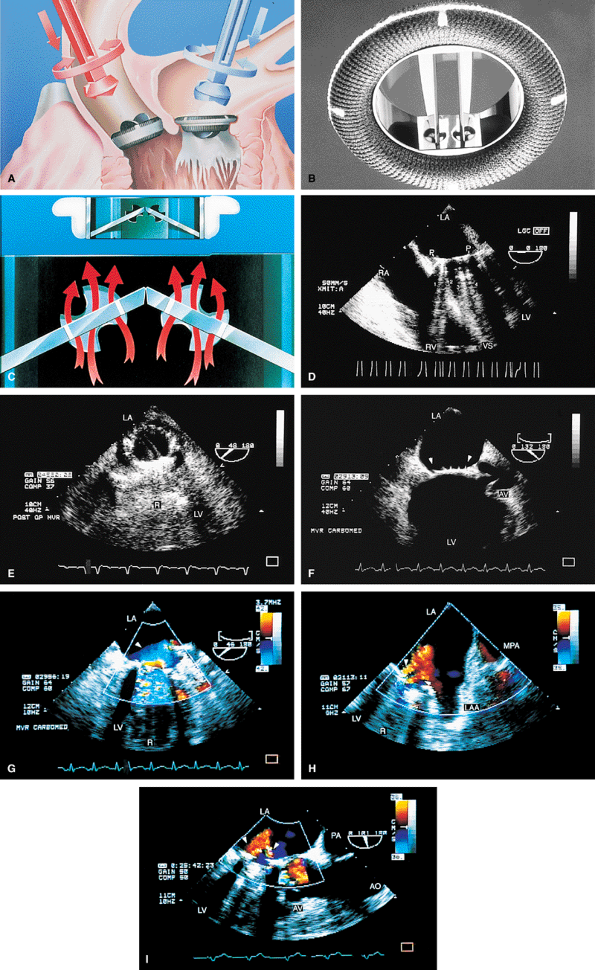

FIGURE 5.1. St. Jude mitral prosthesis: normal. The mitral prosthesis (MP) is seen in the closed (A) and open (B) positions. A. Prosthetic reverberations or artifacts (arrows) that clutter the left ventricle (LV). B. The two leaflets (1 and 2) of the prosthesis in the open position together with the reverberations. C. Aliased diastolic inflow into the LV is seen with a small region of flow acceleration. D–G. Two to three small jets of mitral regurgitation (MR; arrows) are shown. These are normal findings. Usually, these jets are narrow and do not show significant turbulence but may extend deep into the left atrium (LA). G. illustrates the norm (not pansystolic). H. Small linear echoes are normally seen on both the atrial and ventricular aspects of the prosthesis and represent suture material. I, J. Immediately postsurgery, although the patient is still on partial bypass, one leaflet of the prosthesis (P) may intermittently fail to open. This should not be mistaken for dysfunction. When cardiac output improves, normal opening of both leaflets occurs consistently. RV, right ventricle; RA, right atrium. |